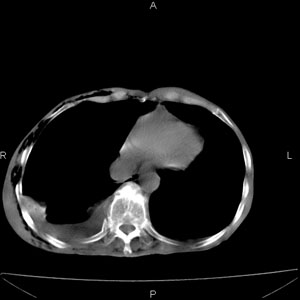

患者男,77岁,于3日前从树上摔下,头部查ct示蛛血,硬膜下出血,上腹部ct未见明显异常,右侧胸腔积液,左侧如常。肺部拍片示右侧肋骨多发骨折住院后今日来查肺部ct,我看到的是1。右侧胸腔血气胸并右肺上叶,中叶压缩性肺不张,2。右肺下叶肺挫伤并多发肋骨骨折,肌内及皮下积气3。左侧少量胸腔积液,我想请教的是3天前左侧胸腔里没有积液今天怎么出现了呢,是什么原因呢?请讨论。